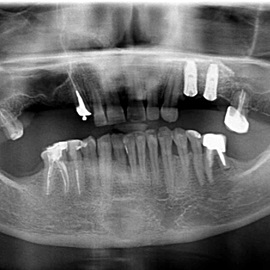

Przedtrzonowce często należą do okolicy estetycznej należy więc zwrócić wzmożona uwagę na poprawną anatomię tkanek kości i dziąsła. Po utracie zęba 25 pacjentka kilka lat chodziła bez jego uzupełnienia, doszło do przesunięcia się zęba 26. U tej pacjentki przed laty był wykonany most jednobrzeżny na czwórce, dość szybko doszło jednak do przeciążenia zęba filarowego, zaniku kości wyrostka i wreszcie pęknięcia korzenia zęba filarowego mostu. Po ekstrakcji i wygojeniu kości stwierdzono ubytek kości wyrostka przekraczający objętość 50% stanu początkowego. Stąd główny nacisk położono na odbudowę tkanek. Uzyskano zadowalający wynik anatomiczny.

Przypadek odbudowy zębów trzonowych z początkowymi znacznymi zanikami kości. Odbudowa kości pionowa i pozioma, następnie implantacja i faza protetyczna.

Pacjentka lat 41, odbudowa protetyczna zębów 24, 25 na implantach - korony porcelanowe na metalu. Po stronie prawej zdjęto most 13 - 16, poprawiono warunki kostne wyrostka zębodołowego i wykonano most na implantach od czwórki do szóstki, oraz nacementowano pojedynczą koronę na kła.

Pacjentka lat 50. Most od zęba 24 do zęba 27. Pękł korzeń zęba filarowego 24. Po ekstrakcji wykonano zabieg odbudowy kości wyrostka zębodołowego i podniesiono zatokę. Następnie po skorygowaniu kształtu i objętości dziąsła przytwierdzonego wykonano pojedyńcze korony na implantach 24, 26, oraz most 13-17